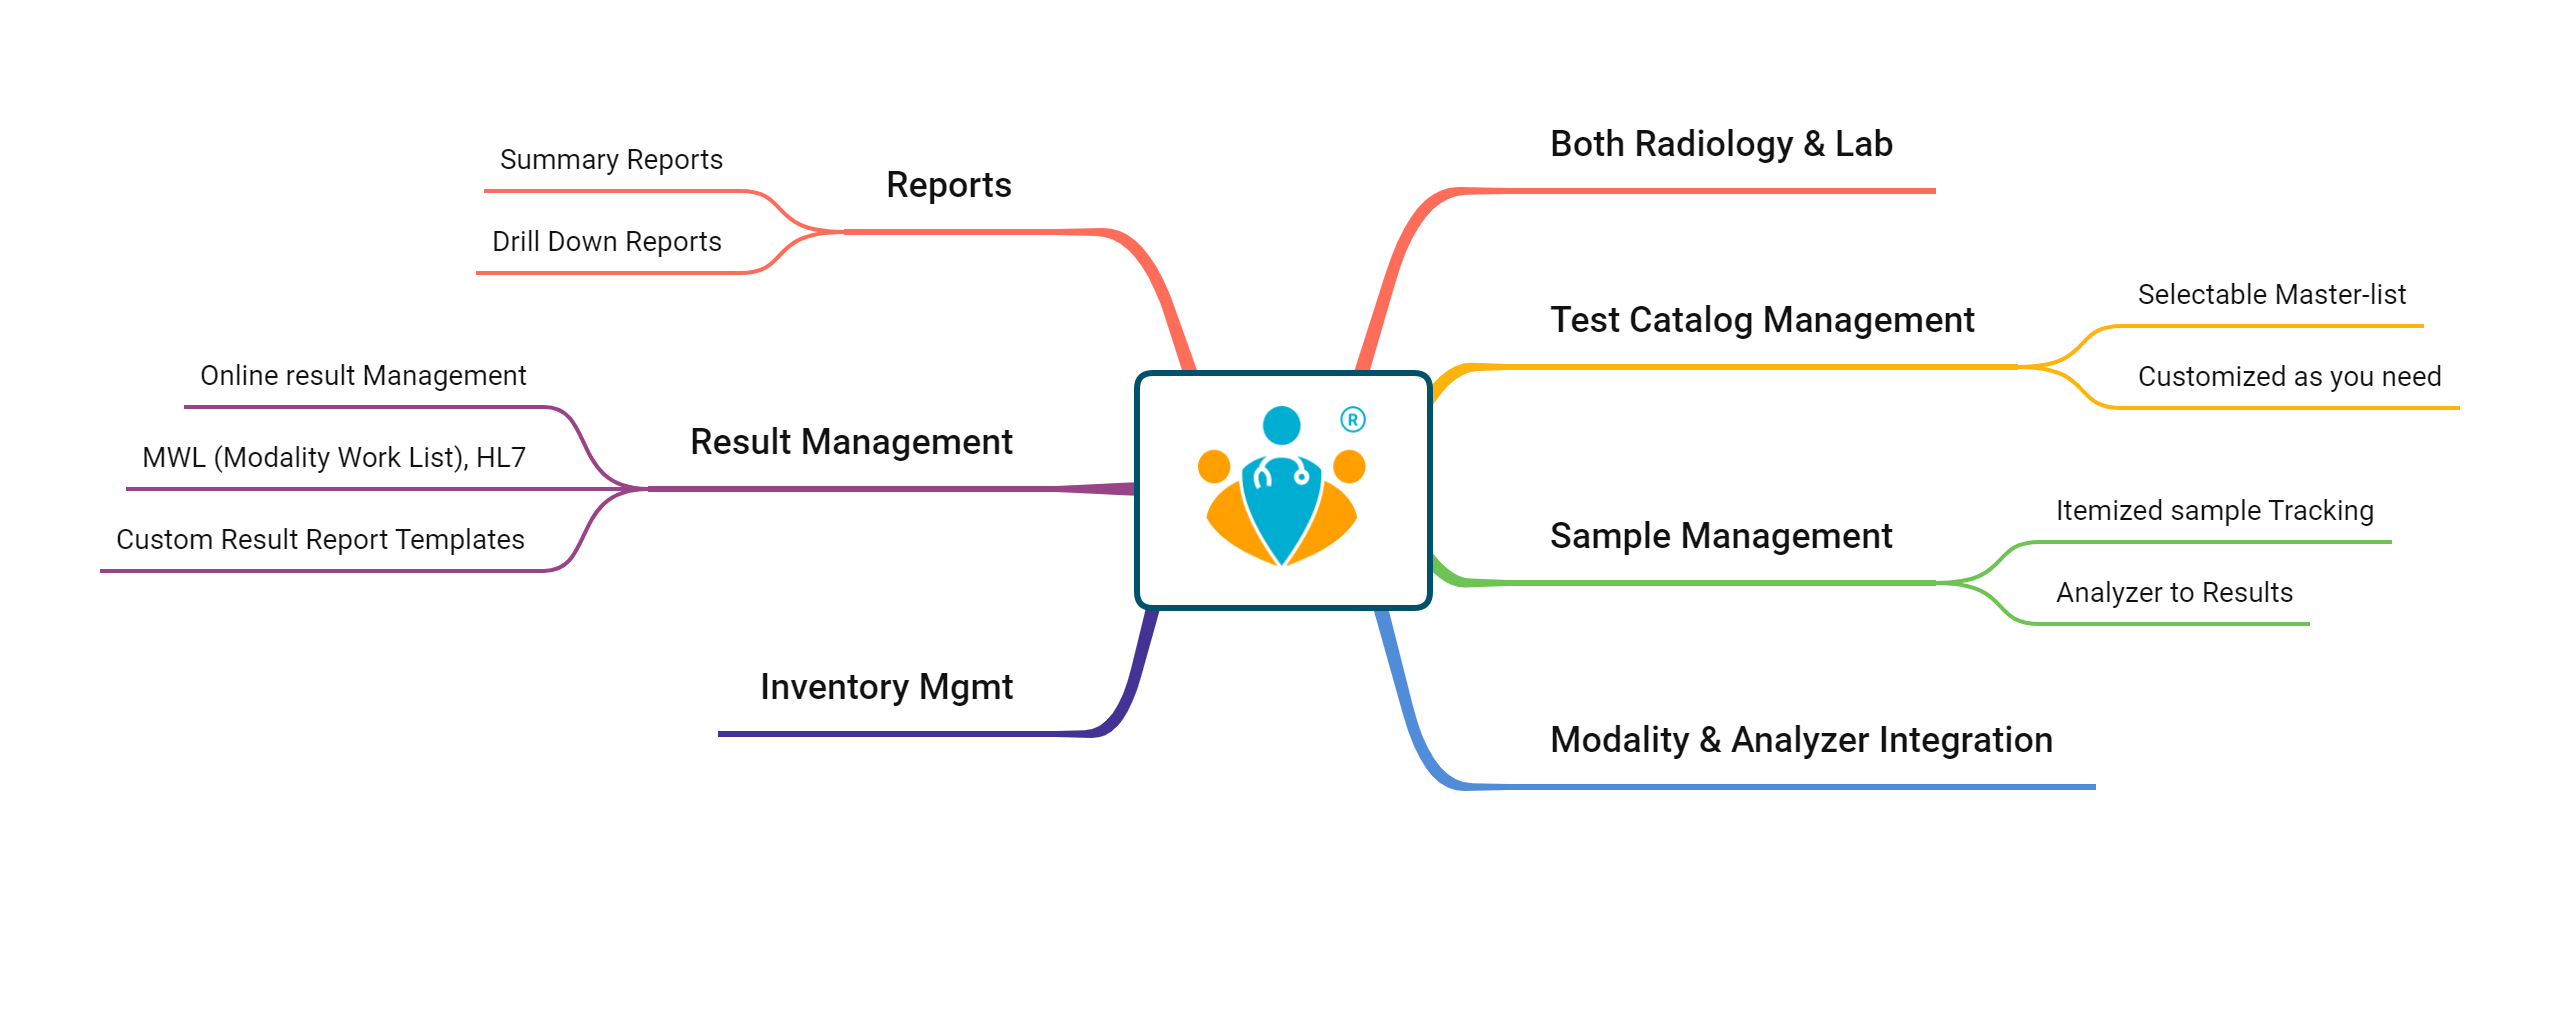

TinyMedic's comprehensive Lab Management solution offers end-to-end features - Investigation Prescription, Billing, Payments, RIS/PACS, Stock Auditing, Accounting, Analytics, and Reporting.

Now automate your workflows for efficiency, accuracy, and patient-centric service. Further, you can track your customers' investigation history and send timely reminders to get further tests done to aid the treatment of chronic conditions.

We serve the need of various pharmacies :

With our solution, you can manage and track all the IP Laboratory orders and auto-update them to the hospital's medical records and the patient's PHRs. We help you handle your OP investigations faster and more efficiently with our support for e-prescriptions and real-time communication. IP investigation or an OP investigation, Our cloud-based solution is integrated with the patient's application for consistent and streamlined medication management.

Investigation reports and relevant scan images get auto-uploaded to the patient's PHR - Personal Health Record application.

TinyMedic's modular solutions for Doctors, Pharmacies, Laboratories, and our integrated platform 'TinyMedic' adhere to HL7 standards for interoperability so that the patient's data across the healthcare providers reflects seamlessly in the patient's Personal Health Record Application.

Additionally, an integrated platform like TinyMedic makes it easier for healthcare professionals to access and manage data from multiple sources quickly and efficiently. For example, Our Hospital Module can manage patient records, billing, scheduling, and other administrative tasks. Similarly, Our Lab Module can track laboratory tests and results, while our Pharmacy Module can help pharmacies manage their inventory and orders.